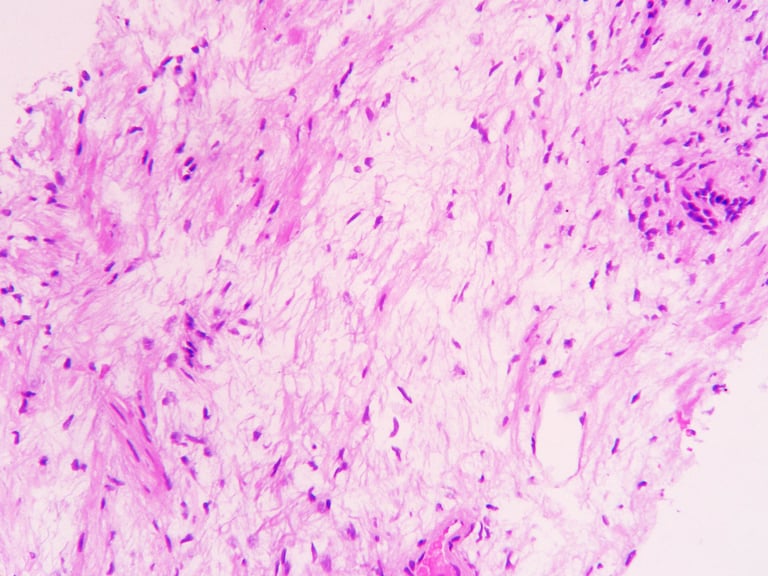

За результатами патогістологічного дослідження після 12-точкової біопсії встановлено діагноз: аденокарцинома передміхурової залози, 6 балів за Глісоном (3+3), G1, із ураженням приблизно 25% тканини у трьох біоптатах.

Повторна біопсія підтвердила наявність чітко окресленої ділянки склерозу в зоні проведеного лікування без ознак злоякісного процесу.